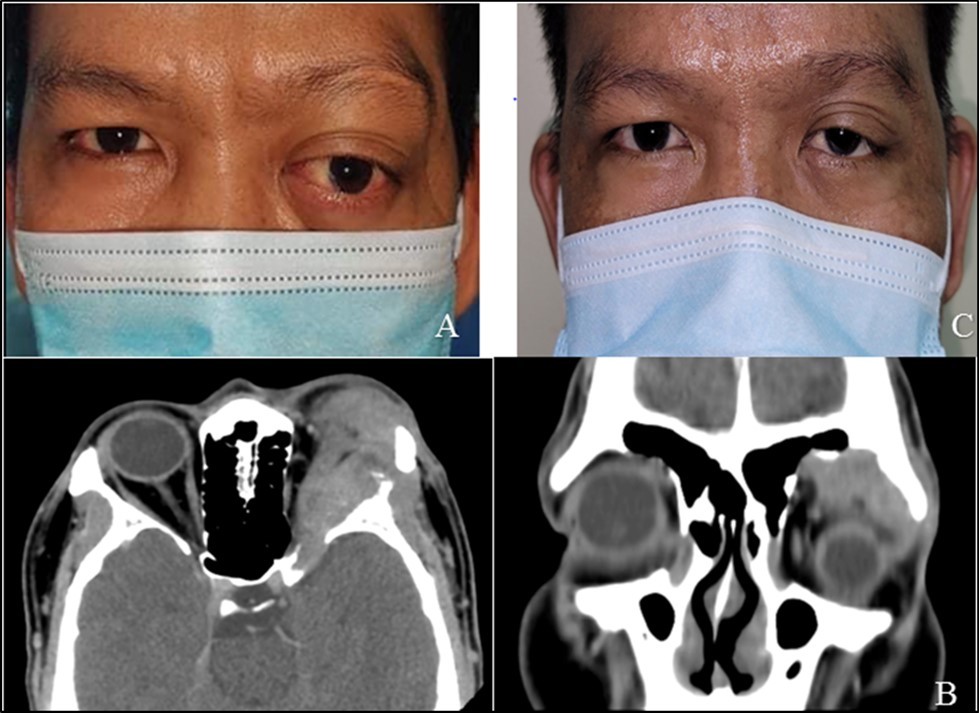

The patient followed two years afterwards due to palpable mass noted on the same site . He was seen by the service again and was referred to Oncology Department. On repeat imaging, there was tumor recurrence with intracranial extension . Systemic work-up revealed pulmonary metastasis. Prognosis was discussed and while exenteration was advised, he was need keen for this and opted for a globe-sparing procedure. A repeat lateral orbitotomy with debulking of the tumor was done. He continues to undergo chemotherapy (on 5th cycle) and follow up . Figure 4, Figure 5

Figure 5A.Patient seen two years after the first orbitotomy and tumor excision, with recurrence of mass in the superotemporal orbit and globe displacement. B. Orbital CT scan (axial and coronal sections) revealed a 2.2 x 2.4 x 3.3 cm lobulated, heterogeneously enhancing soft tissue mass seen centered in the left lacrimal gland with few punctate calcifications and associated lytic changes of the adjacent left frontal bone that are suggestive of tumor recurrence C. Four months post-op after repeat orbitotomy and debulking of tumor with chemotherapy